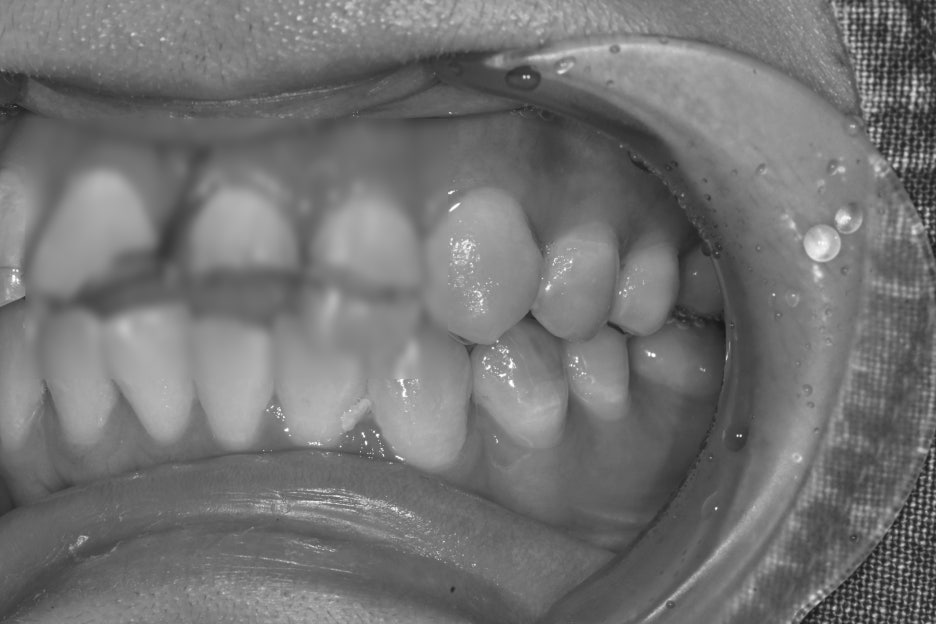

Before and after treatment photos

Photos before and after treatment